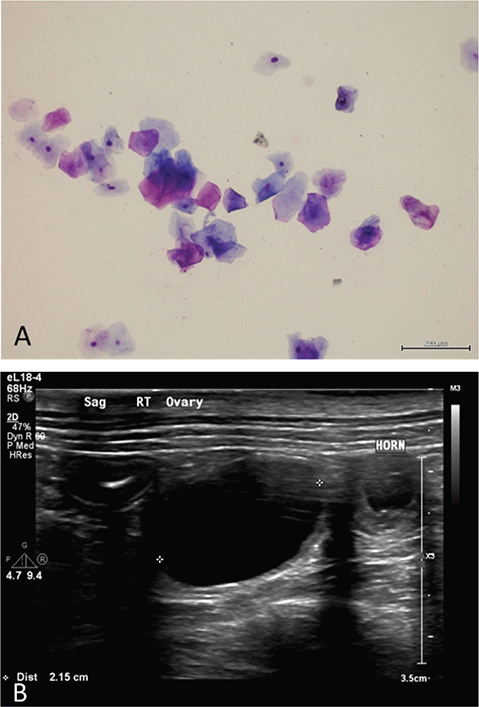

Dog weighed 23 kg with a body condition score of 4/9. Physical examination revealed minimal to no vulvar edema with no vulvar discharge. Mammary glands palpated within normal limits with 5 nipples on the left mammary chain and 4 nipples on the right mammary chain. All other physical examination findings were unremarkable. Digital vaginal examination was normal (no abnormalities in the caudal vaginal vault nor evidence of foreign material) and vaginal lavage appeared normal. Serial vaginal cytologic examinations over the next 2 months identified cytological estrus (vaginal epithelial cells exhibiting > 80-90% cornification of superficial and anuclear epithelial cells) without evidence of inflammation (Figure 2A).9 Serum progesterone concentrations were 0.336 ng/ml. Abdominal ultrasonography revealed bilateral cystic structures within gonads; right gonad had a 2.1 x 1.6 cm ovoid anechoic cyst and left gonad had an 8 mm cystic structure. Uterus was identified from the cervix to the uterine horns and demonstrated diffuse endometrial hyperplasia with multifocal cystic structures throughout the endometrial wall. Proximal right uterine horn additionally contained a focal amount of anechoic intraluminal fluid (Figure 2B).

Figure 2.

Figure 2. Vaginal cytology (A) and transabdominal ultrasonography image (B) at initial cystic aspiration; note cornified vaginal epithelial cells composed of superficial and large intermediate cells (20 x magnification; bar = 200 µm) and large cystic structure in right gonad and intrauterine fluid in right uterine horn.